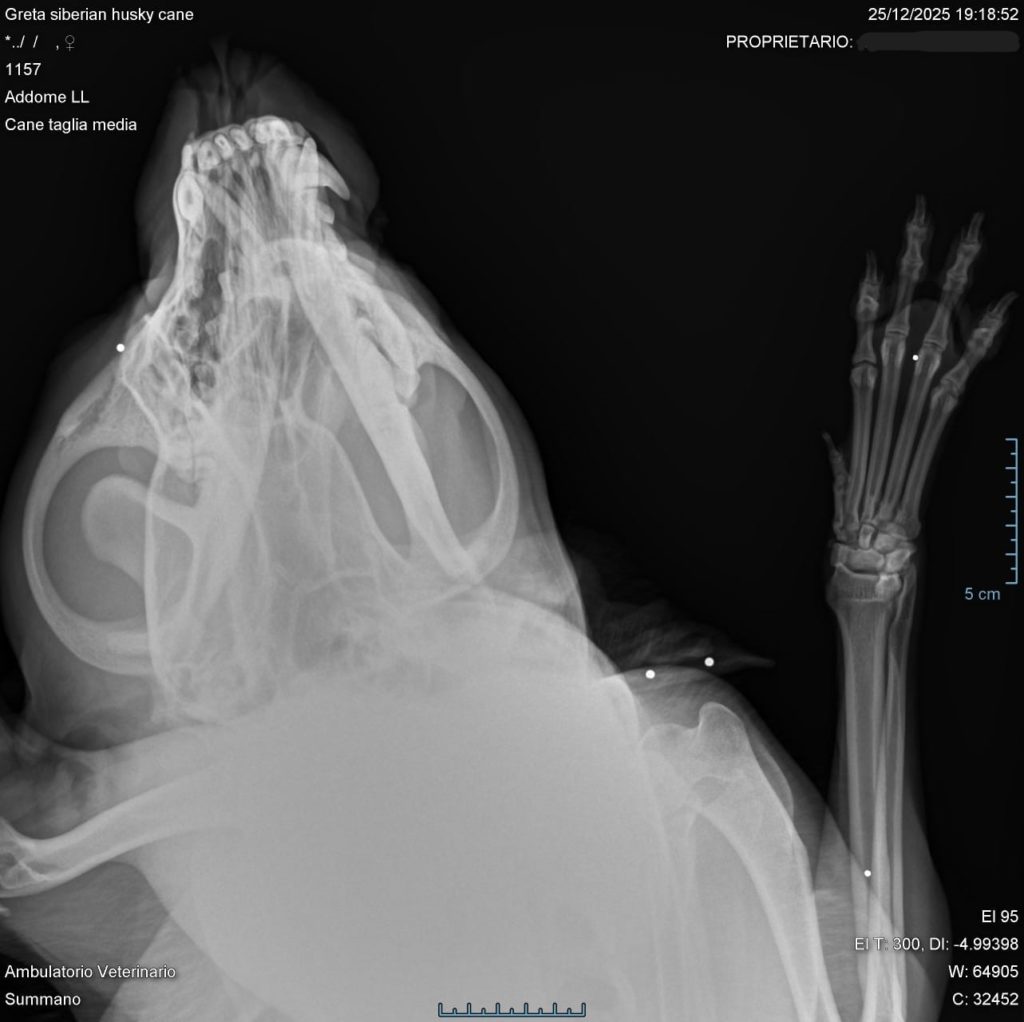

Secondo quanto ricostruito dalla ragazza, i cani – probabilmente spaventati da qualche rumore molesto e trovando il cancelletto socchiuso – si sarebbero allontanati di casa attorno alla mezzanotte. Pochi minuti dopo Angrete era già sulle sue tracce, ma è qui che accade l’inspiegabile: tre spari, in rapida successione, squarciano il silenzio. Greta rincasa dopo qualche minuto, atterrita e sporca di sangue, la “sorella” purtroppo no. Le ricerche proseguono, ma senza esito e l’indomani la proprietaria si rivolge ad una clinica veterinaria per appurare eventuali ferite: “Greta aveva addosso nove pallini in piombo – spiega la ragazza di Valli – fortunatamente subiti di rimbalzo. Questo ci ha quindi confermato che davvero qualcuno aveva sparato, intenzionalmente, in direzione dei cani con la volontà di ferire mortalmente”.